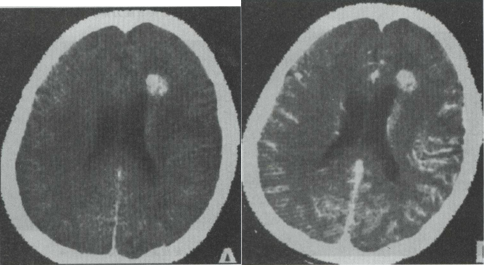

27.女性,40岁。CT发现额叶异常密度灶,无任何症状及体征。CT诊断(见图)最大可能是 ()